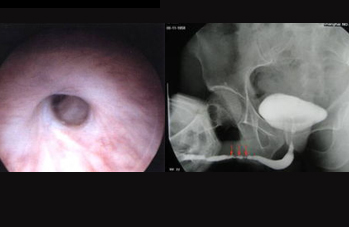

尿道狭窄